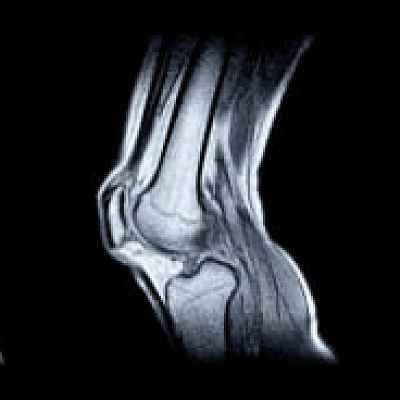

Диагностика кисты мениска — это работа ортопеда-травматолога или хирурга. Для выставления диагноза врач опрашивает пациента, исследует анамнез. Пальпирует и осматривает пораженную область, получает представление о вероятном характере патологического процесса. Основу диагностики составляют инструментальные обследования. Применяется серия методик:

- УЗИ коленного сустава, при кисте мениска способ дает достаточно информации о характере расстройства;

- МРТ при кисте мениска используется, если полученных клинических данных недостаточно, требуется уточнить характер, степень выраженности патологического состояния;

- артроскопия: ее назначают редко, поскольку это инвазивное исследование.

Если имеются данные за развитие артроза, необходима рентгенография или, в крайних случаях, компьютерная томография. Выбор тактики обследования — это работа специалиста.